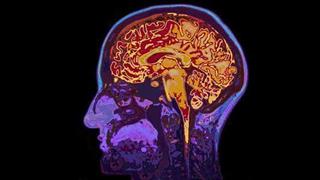

Η ελβετική φαρμακοβιομηχανία Roche Holding AG, ανακοίνωσε ότι νέα έρευνα για το αντινεοπλασματικό φάρμακο Avastin, έδειξε ότι παρέτεινε σημαντικά την επιβίωση χωρίς εξέλιξη της νόσου σε ανθρώπους με επιθετική μορφή καρκίνου στον εγκέφαλο.

Η φάσης ΙΙΙ έρευνα, AVAglio, ανταποκρίθηκε σε έναν από τους κύριους στόχους της βελτίωσης της επιβίωσης χωρίς επιδείνωση της νόσου σε ανθρώπους με γλοιβλάστωμα, ανακοίνωσε η εταιρεία στις 10 Αυγούστου.

Η Roche ανακοίνωσε ότι η συγκεκριμένη έρευνα έδειξε ότι άνθρωποι με γλοιοβλάστωμα, ιδιαίτερα επιθετικό τύπου καρκίνου, χωρίς πολλές επιλογές όσον αφορά την αντιμετώπιση, έζησαν σημαντικά περισσότερο χωρίς επιδείνωση της νόσου όταν το Avastin προστέθηκε σε ακτινοβολίες και χημειοθεραπεία με temozolomide.